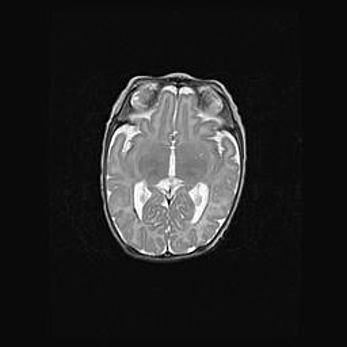

Сообщающаяся гидроцефалия. Кистозная энцефаломаляция головного мозга.

Возраст: 3 месяца 4 дня

Вес: 3100 г

Пол: женский

Окружность головы: 34 см

Срок гестации: 31 неделя

Кистозная энцефаломаляция головного мозга - одна из форм поражения головного мозга в детском возрасте. Характеризуется возникновением множественных и распространённых кист в коре, белом веществе и подкорковых образованиях головного мозга у плодов, новорождённых и детей раннего возраста. Развитие кистозной энцефаломаляции связано с внутриутробной асфиксией и гипотонией, родовой травмой, тромбозом синусов, пороками развития сосудов, инфекциями, сепсисом и другими причинами. Наиболее значимые инфекционные агенты: вирусы простого герпеса, цитомегалии, краснухи, токсоплазмы, энтеробактерии, золотистый стафилококк и другие.